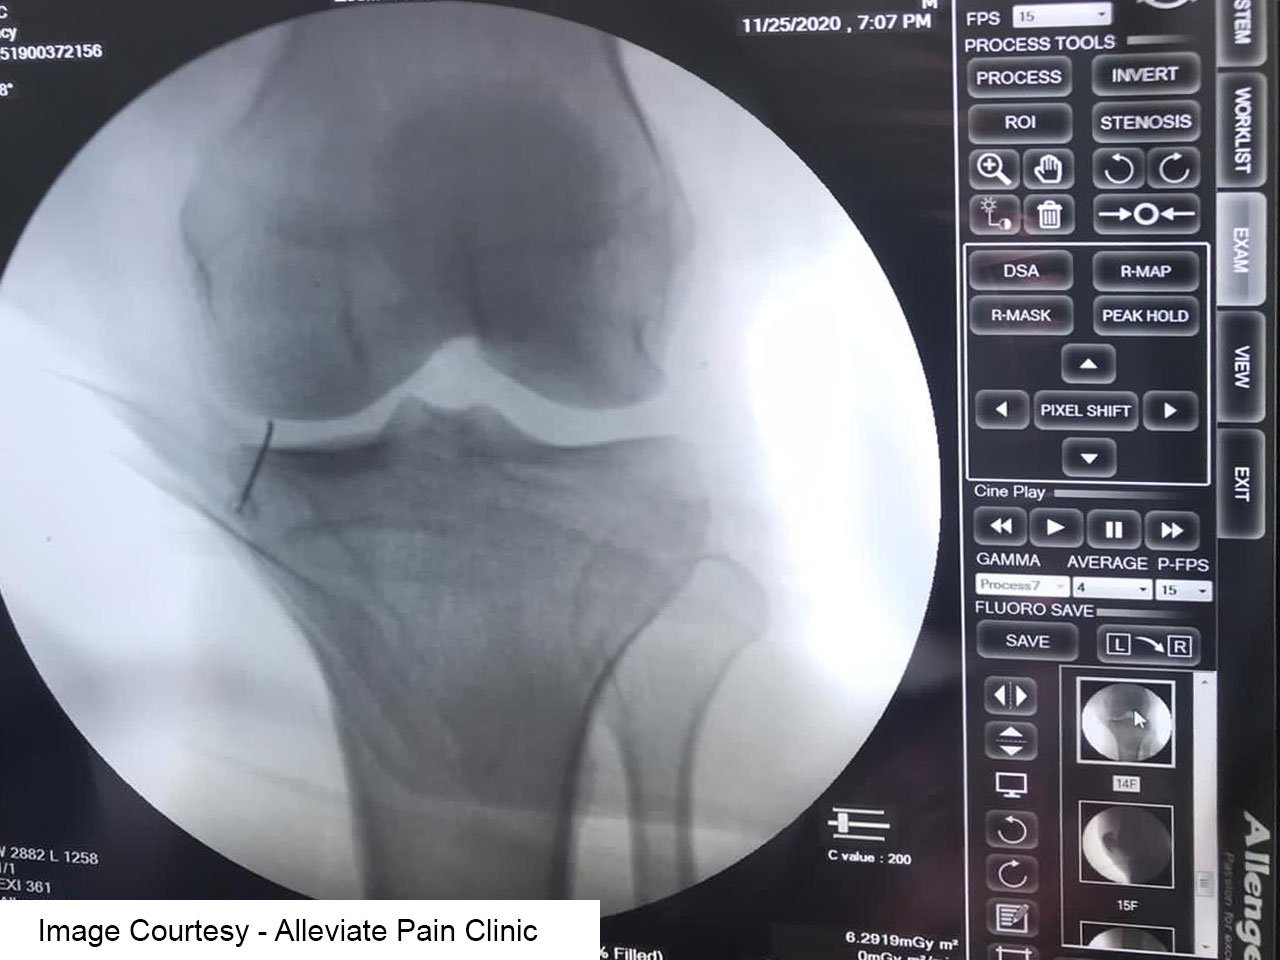

Fluoroscopy-Guided PRP Therapy

Fluoroscopy is a real-time imaging technique that uses continuous X-ray beams to visualize internal structures of the knee joint. It provides dynamic imaging, allowing our medical professionals to monitor the injection process in real-time.

Precise Needle Placement

Fluoroscopy guidance enables our practitioners to accurately position the needle within the target area of the knee joint, ensuring the precise delivery of PRP to the affected tissues. Platelet rich plasma

Visualization of Anatomical Structures

Fluoroscopy provides clear visualization of bony structures, soft tissues, and joint spaces, facilitating the identification of anatomical landmarks and potential areas of pathology within the knee joint.

Real-Time Monitoring

With fluoroscopy, our healthcare providers can monitor the dispersion of PRP within the joint space, ensuring uniform distribution and optimal coverage of the affected areas.